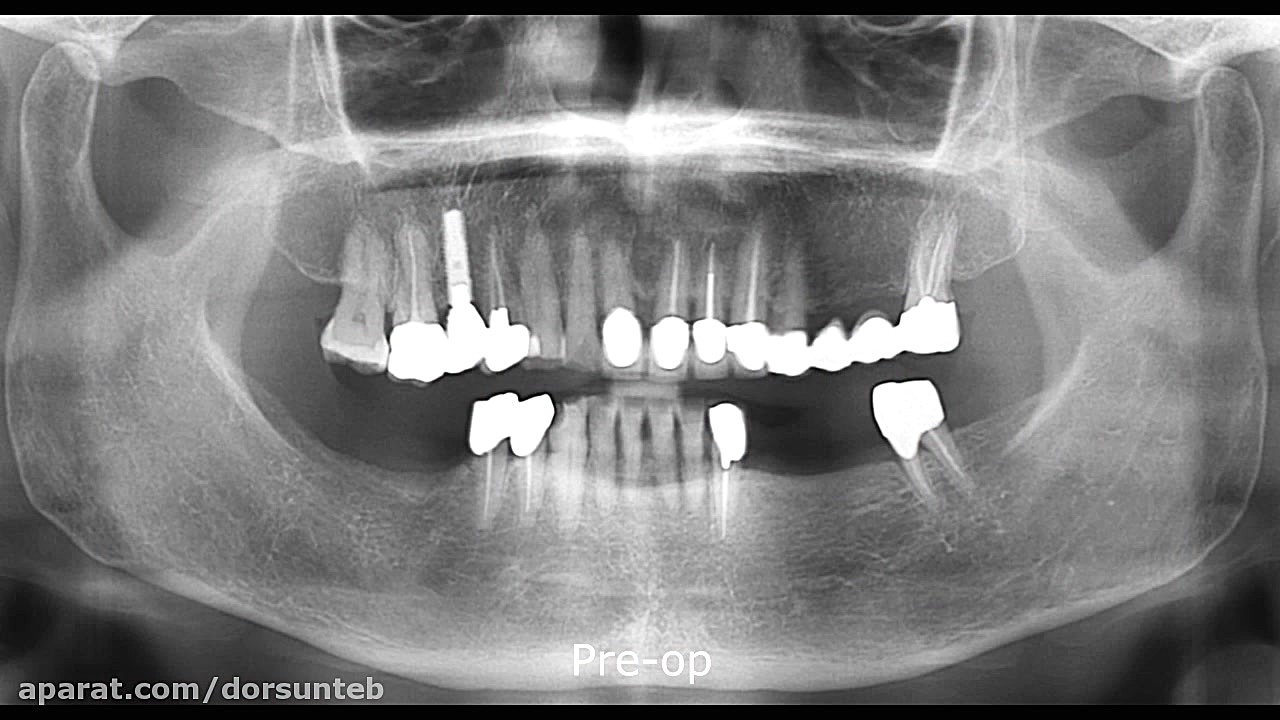

Immediate implantation using Implant Guide2